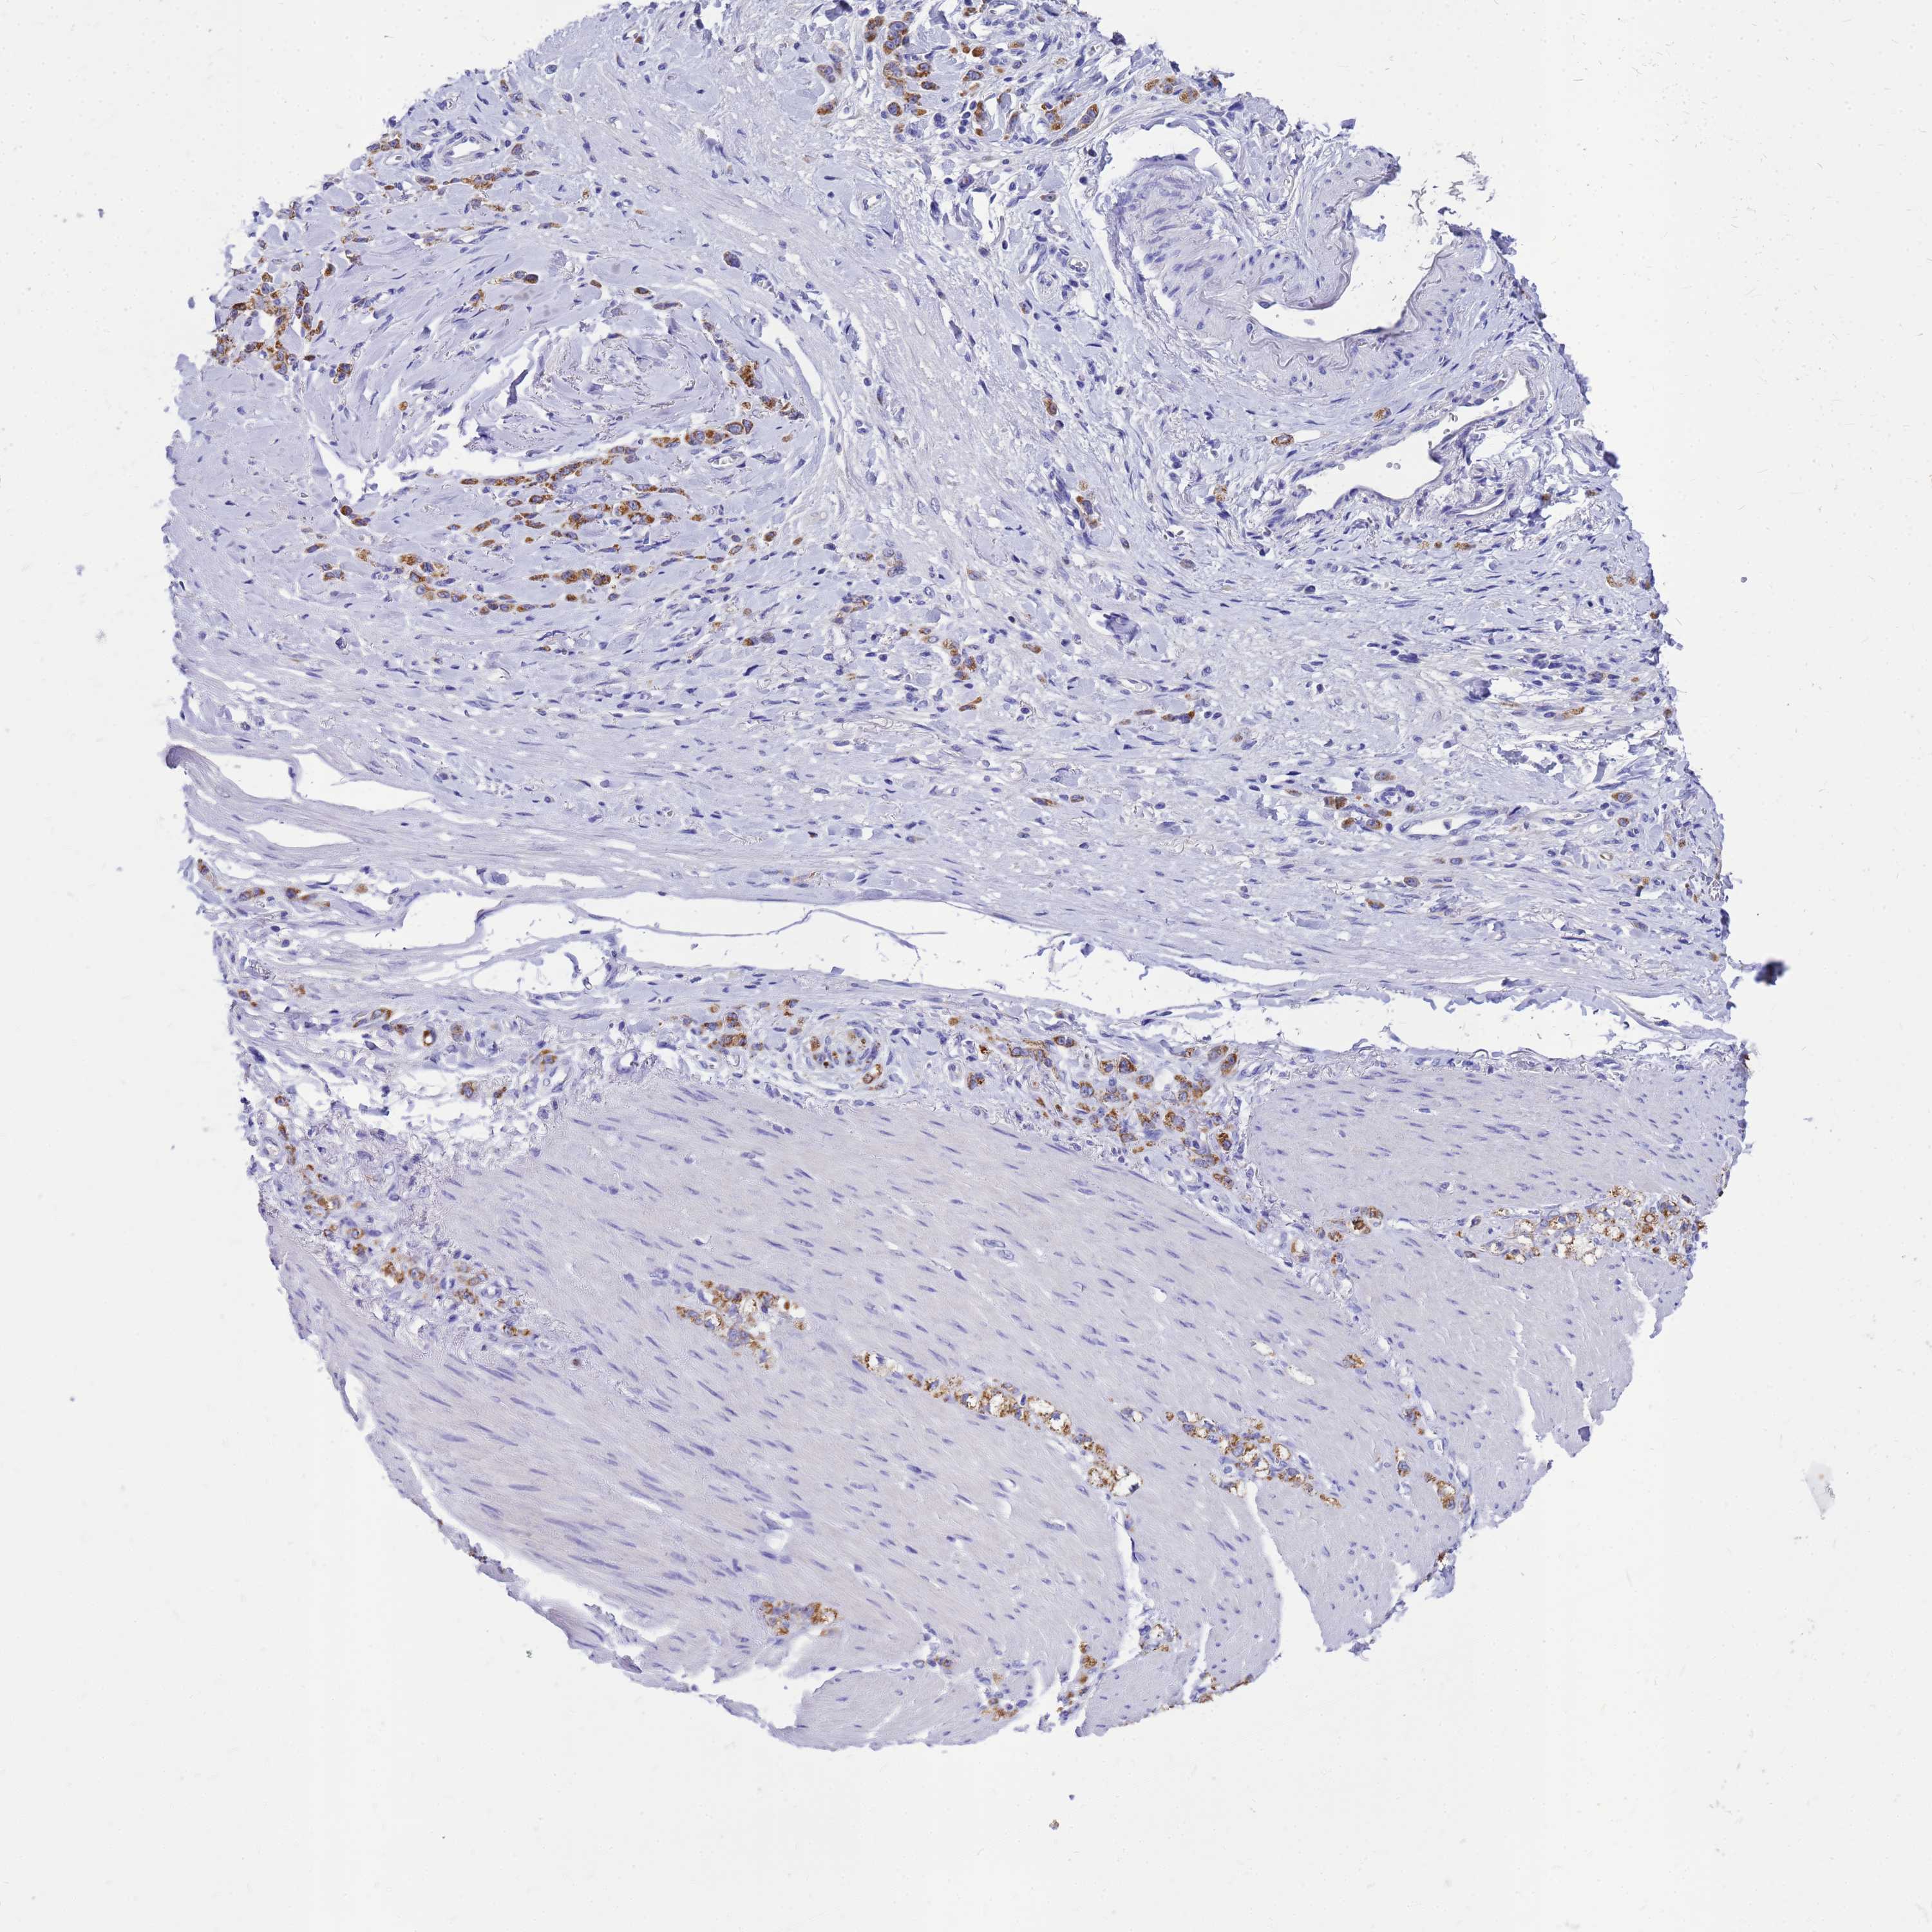

STOMACH CANCER - Protein expressioni

A mouse-over function shows sample information and annotation data. Click on an image to view it in a full screen mode. Samples can be filtered based on level of antibody staining by selecting one or several of the following categories: high, medium, low and not detected. The assay and annotation is described here.

Note that samples used for immunohistochemistry by the Human Protein Atlas do not correspond to samples in the TCGA dataset.

Antibody stainingi

Antibody staining in the annotated cell types in the current human tissue is reported as not detected, low, medium, or high, based on conventional immunohistochemistry profiling in selected tissues. This score is based on the combination of the staining intensity and fraction of stained cells.

Each image is clickable and will lead to virtual microscopy that enables deeper exploration of all samples and also displays staining intensity scores, fraction scores and subcellular localization as well as patient and tissue information for each sample.

Antibody HPA045748

Staining

High

Medium

Low

Not detected

Intensity

Strong

Moderate

Weak

Negative

Quantity

>75%

75%-25%

<25%

None

Location

Nuclear

Cytoplasmic/membranous

Cytoplasmic/membranous,nuclear

Adenocarcinoma, NOS